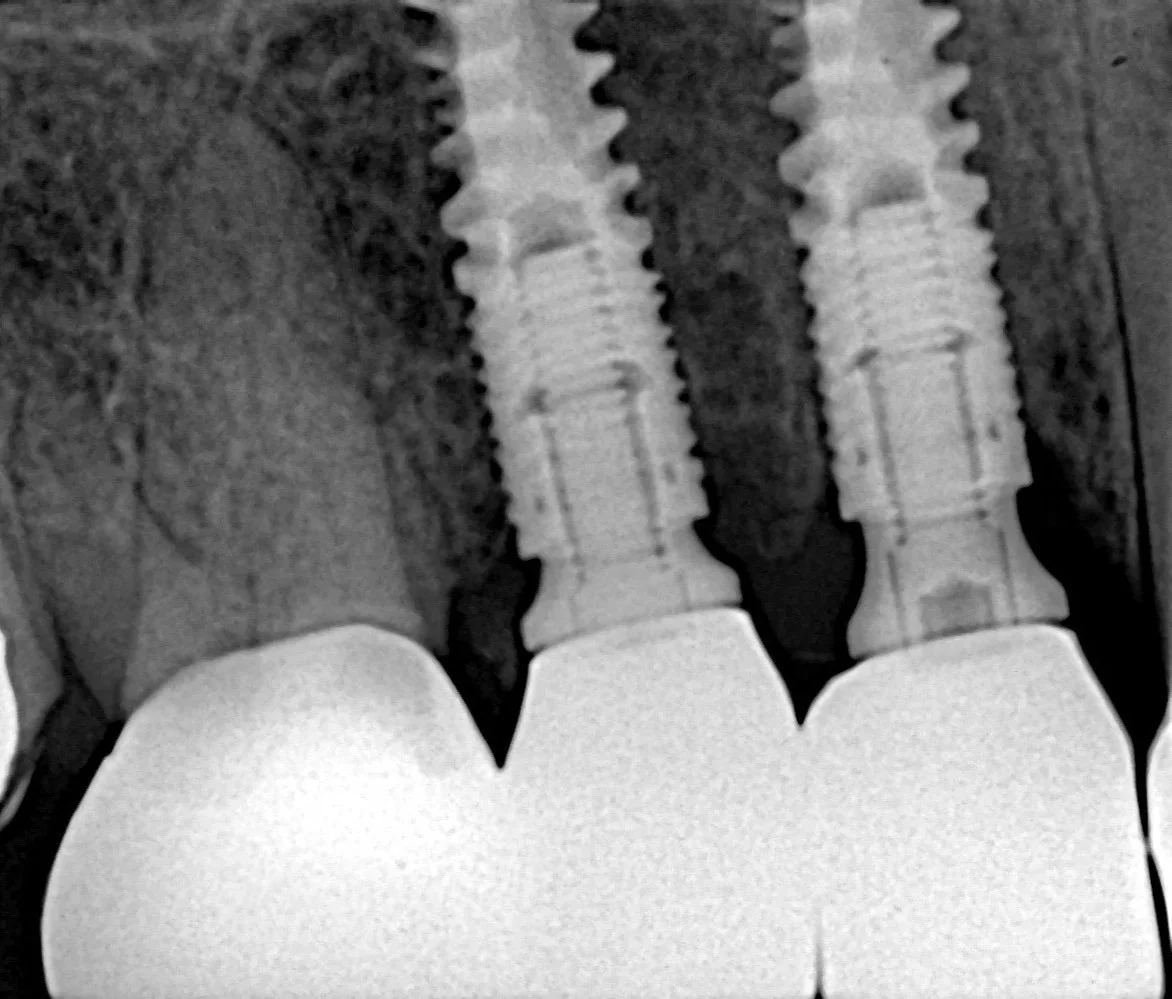

This phase is the easiest part of the whole procedure, as it is direct application of the previous one. The entire phase took only less than 30 minutes. Post-operative X-rays confirmed perfect implant positioning and parallelism.